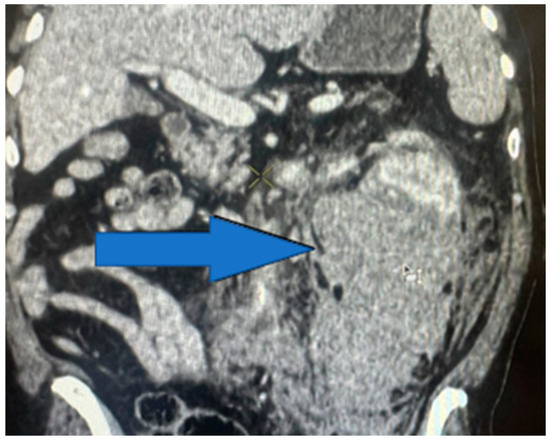

The distribution of the renal injuries, according to AAST classification (Figure 5), in this study is the following: grade 1 (Figure 6) (26.97%), grade 2 (Figure 7) (34.83%), grade 3 (Figure 8) (19.10%), grade 4 (Figure 9) (10.11%), and grade 5 (Figure 10 and Figure 11) (8.99%).

Figure 9. Contrast-enhanced CT scan showing left-kidney grade 4 injury—parenchymal laceration.